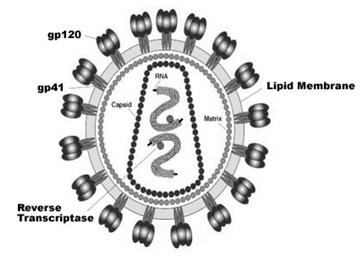

Alzheimer’s disease has been identified as a protein misfolding disease caused by the accumulation of abnormally folded A-beta and tau proteins in the brain. Plaques are made up of small peptides, 39–43 amino acids in length, called beta-amyloid (also written as A-beta or Aβ). Beta-amyloid is a fragment from a larger protein called amyloid precursor protein (APP), a transmembrane protein that penetrates through the neuron’s membrane. APP is critical to neuron growth, survival, and post-injury repair.

In Alzheimer’s disease, an unknown process causes APP to be divided into smaller fragments by enzymes through proteolysis. One of these fragments (Aβ peptide) gives rise to beta-amyloid fibrils, which form clumps that deposit outside neurons in dense formations known as senile plaques. (Figure-1)

AD is also considered a tauopathy due to abnormal aggregation of the tau protein. Every neuron has a cytoskeleton, an internal support structure partly made up of structures called microtubules. These microtubules act like tracks, guiding nutrients and molecules from the body of the cell to the ends of the axon and back. A protein called tau stabilizes the microtubules when phosphorylated and is, therefore, called a microtubule-associated protein. In AD, tau undergoes hyperphosphorylation.

The hyperphosphorylated tau protein begins to pair with other threads, creating neurofibrillary tangles, thus disintegrating the neuron’s transport system.

Figure-1 -showing amyloid plaques and neurofibrillary tangles in Alzheimer’s disease.